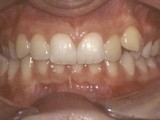

Zkřížený skus, předkus, nedostatek místa pro špičák. Léčba pomocí aparátu Hyrax a dále fixními aparáty v obou čelistech s jumping aparátem. V ústech přítomné MARA-stopy na dočasnou stabilizaci výsledku.

Před léčbou        Po léčbě

přední pac2        přední pac2